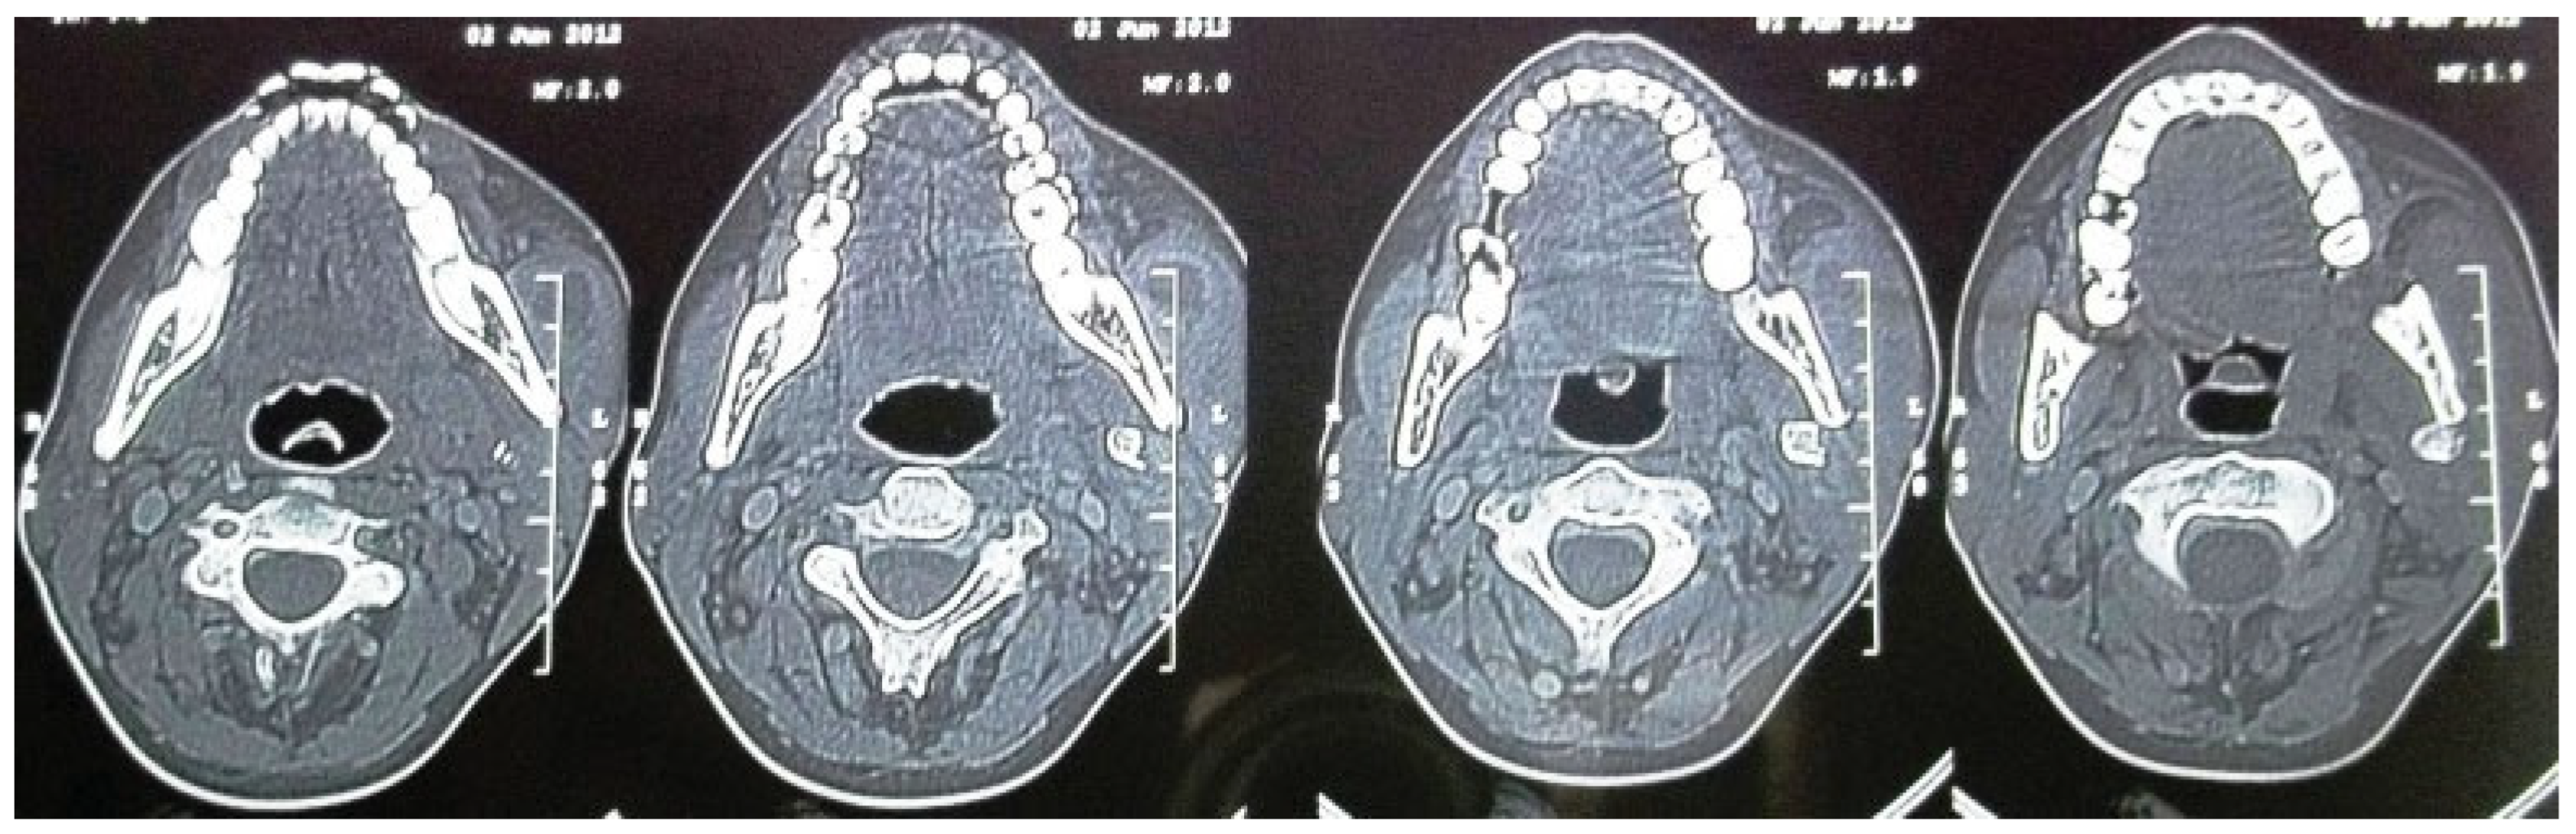

A Rare Case Report of an Unusual Dislocation of Fractured Mandibular Condyle

Mishra, M.; Singh, G. A Rare Case Report of an Unusual Dislocation of Fractured Mandibular Condyle. Craniomaxillofac. Trauma Reconstr. 2016, 9, 166-169. https://doi.org/10.1055/s-0035-1566161